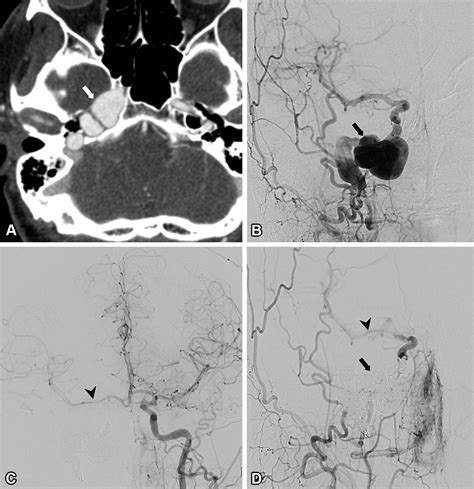

• Arteriovenous Malformations (AVMs): These are abnormal connections between arteries and veins that can create high-pressure, turbulent flow.

• Venous Sinus Stenosis: Narrowing of the venous sinuses—the large veins that drain blood from the brain—is a very common cause of pulsatile tinnitus.

• Glomus Tumors: Though usually benign, these are vascular tumors that grow near the middle ear and can cause a loud, rhythmic thumping sound.

During your appointment, a specialist will likely perform a physical examination of your ears and neck. They may order imaging tests, such as an MRI, MRA (Magnetic Resonance Angiography), or CT scan, to visualize the blood vessels and structures near your ear. These imaging techniques are the "gold standard" for uncovering the precise pulsatile tinnitus causes that may be affecting you.